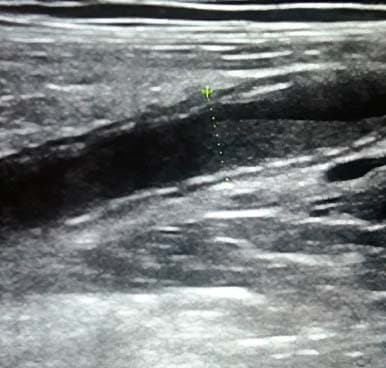

Воспаленный аппендикс не поддается компрессии, поэтому его размер и форма остаются прежними (трубчатая структура на продольном скане и круглая на поперечном) (см. рис. 4).

Рисунок 4. Оценка сжимаемости.